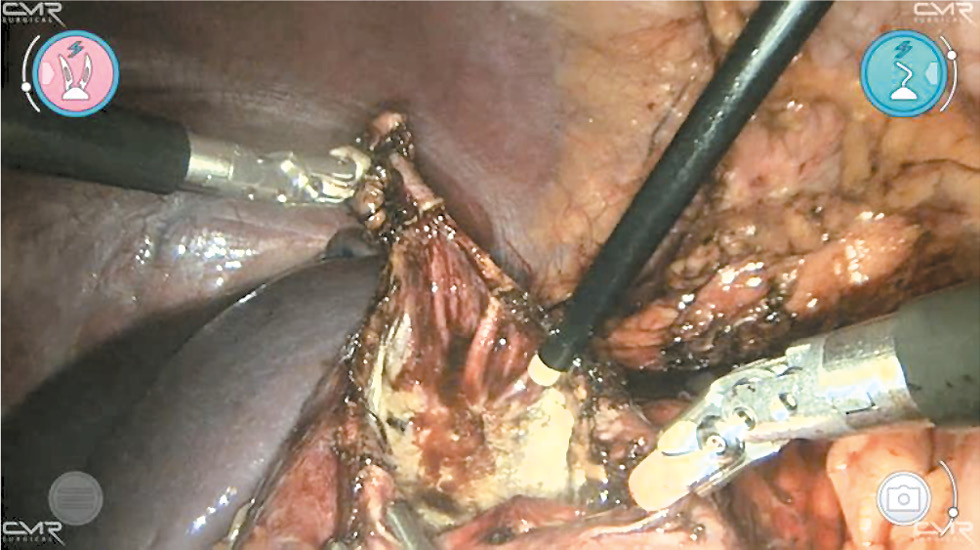

В зависимости от стороны поражения процедуру начинают с мобилизации восходящего или нисходящего отделов толстой кишки, которую затем перемещают медиально, чтобы обнажить почку. После рассечения околопочечной фасции и обнажения кисты оболочку кисты аккуратно надсекают и аспирируют жидкость. Большую часть стенки кисты, возвышающейся над тканью почки, иссекают с помощью биполярного зажима по границе аваскулярной зоны, чтобы предупредить кровотечение из почечной паренхимы, и отправляют на гистологическое исследование (рис. 2). Внутреннюю выстилку кисты подвергают аргон-плазменной коагуляции (рис. 3). В резидуальную полость устанавливают дренажную трубку, которую удаляют, когда прекращается поступление экссудата.

Рис. 2. Робот-ассистированное лечение кисты почки: этап фенестрации наружной порции кисты.

Fig. 2. Robot-assisted treatment of renal cyst: the stage of fenestration of the outer portion of the cyst.